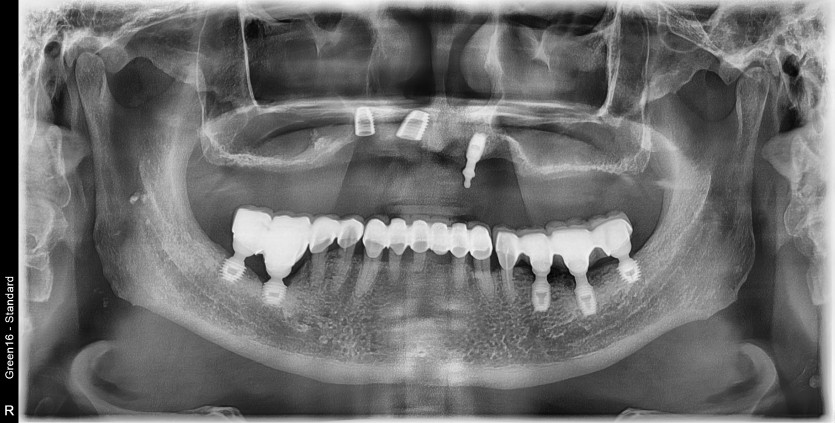

#12.13.22 타원 임플란트 제거 후

임플란트 수술+치조골 이식술 시행하였습니다.